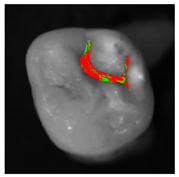

The classification model generated by the fine kNN algorithm was used to classify the fissural systems of five additional teeth, which were not included in the training and evaluation of the algorithm (Table 3). The projection maps show that the classified enamel state is in good agreement with the PLM images in the histologically validated area: Stained samples show a nearly homogeneous distribution of the predicted enamel state “stained”. However, some clearly circumscribed regions away from the histologically validated area are classified as “stained lesion”. Stained lesion samples exhibit a more heterogeneous distribution of enamel health states: A large proportion of fissural areas are classified as “stained lesion”; however, there are numerous “stained” regions of varying sizes dispersed in between.

Table 3.

Clinical simulation of enamel health predictions using HSI-based automated classification as a decision-support system. Five additional teeth (two stained [(a) and (b)], three stained lesion [(c) through (e)]) were imaged and classified by the previously trained fine kNN classification algorithm (i.e., the samples in this table were not included in algorithm training). Stained sound enamel is displayed green, whereas lesions (stained or unstained) are displayed red. Polarization microscopy images from each tooth’s sectional plane (dotted lines) serve as reference. All scale bars = 1 mm.